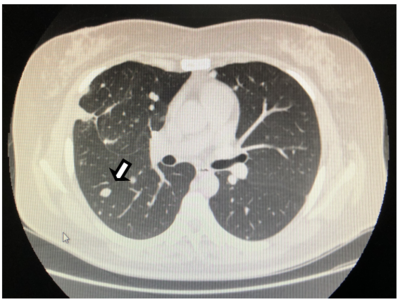

2019年初,一个很冷的早晨,她感冒起床,咳嗽,痰中带血。在家人陪同下,到中国人民解放军总医院海南分院复查。CT结果显示左肺上叶纵隔及胸膜下见斑片,边界不清。双肺下叶增加一个直径约7mm的磨玻璃小结节,边界清晰。这次陈女士慌了,担心是肺癌。她想马上手术切除肺结节,但很多医生都拒绝了。医生说很可能是良性的,建议随访。